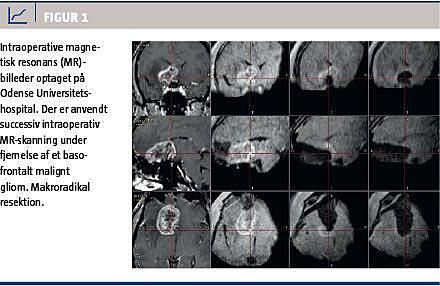

Foruden systemets elegante integration med bNeuN, anvendes iMRI til successiv resektionskontrol under hjernetumoroperationer, og der er på Odense Universitetshospital nu blevet opereret over 100 patienter under anvendelse af iMRI. Patienternes lidelser var fordelt på glioblastomer (Figur 1), lavgradsgliomer og hypofyseadenomer; teknikken giver fremragende visualisering af de transsfenoidale forhold, herunder chiasma opticums successive dekompression. Det er i et prospektivt, randomiseret studie blevet påvist, at brugen af iMRI optimerer resektionsgraden af maligne gliomer [2].